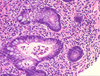

What is seen here?

Pseudomembranous colitis

- Higher magnification of volcano eruption of neutrophils and dead cells